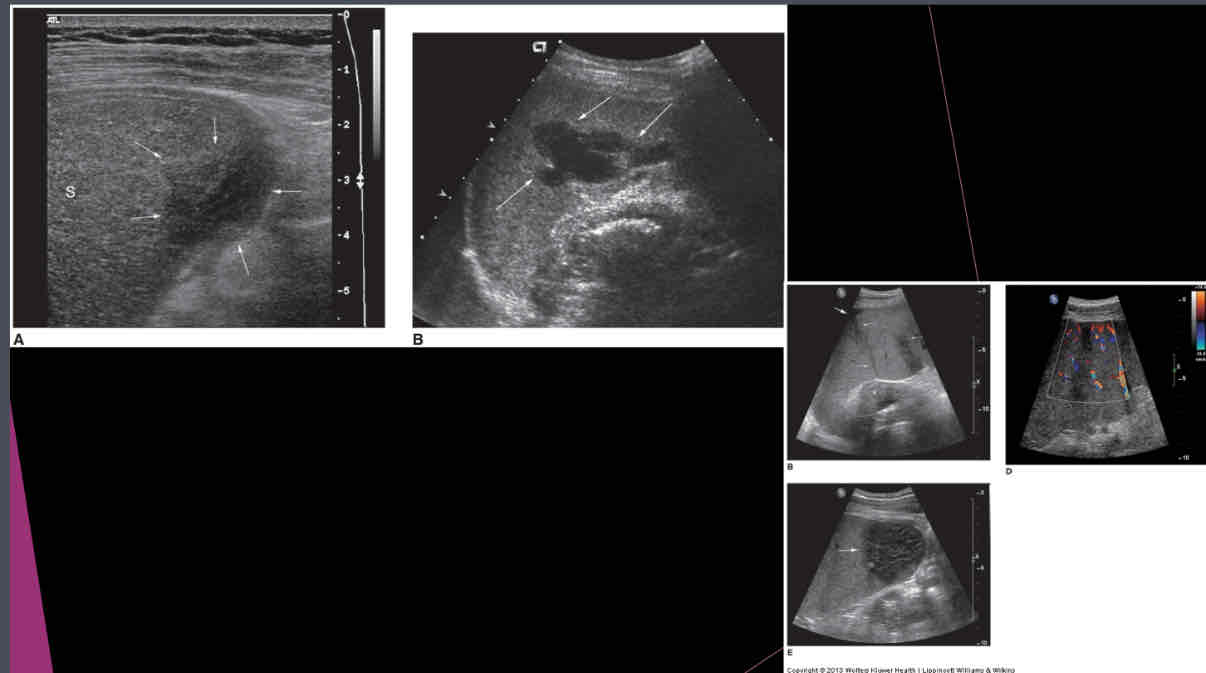

What does the following describe?

•It is rare. May be associated with endocarditis, septicemia and trauma

•May see them status post splenectomy

•Symptoms include pain, dizziness, faintness,

•Lab Testing: decreased hematocrit, fever, increased WBC and possible septicemia

splenic abscess

What does the following describe?

•Sonographically: Complex fluid collection with internal echoes

•Irregular borders

•May see septations and pleural effusion

•Dirty shadowing from gas producing organisms

splenic abscess

What does the following describe?

•Areas of tissue death, blood supply is cut off

•Found in patients with leukemia, sickle cell anemia, pancreatitis, bacterial endocarditis

•Calcification is last change

splenic infarct